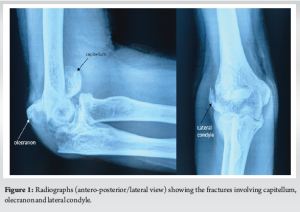

A 65-year-old woman, from a poor socioeconomic background, presented to the outpatient department with pain and swelling over the right elbow for the past 2 days. The patient gave a history of fall at home on a flexed elbow and sustained a closed injury to the right elbow. Following fall, she was unable to move her arm and complained of severe pain. She was taken to an indigenous bone setter where primary treatment in the form of local splints was applied. Having no relief in pain over the next few days, the patient presented to us seeking relief. She was a known diabetic on medications. Initial clinical examinations revealed diffuse swelling over the right elbow with bruising over the posterior and lateral aspects. Tenderness was elicited around all the elbow bony prominences with a restricted range of motion at the affected elbow joint. There was no neurovascular deficit in the affected extremity. Radiographic assessment of the elbow (anteroposterior [AP]/lateral) revealed fractures involving the olecranon, a “double–arc” shadow depicting capitellum fracture on the lateral view, and lateral condyle fracture on AP view. The patient was advised to undergo higher imaging (computed tomography), but it was not affordable for any further investigations (Fig. 1).